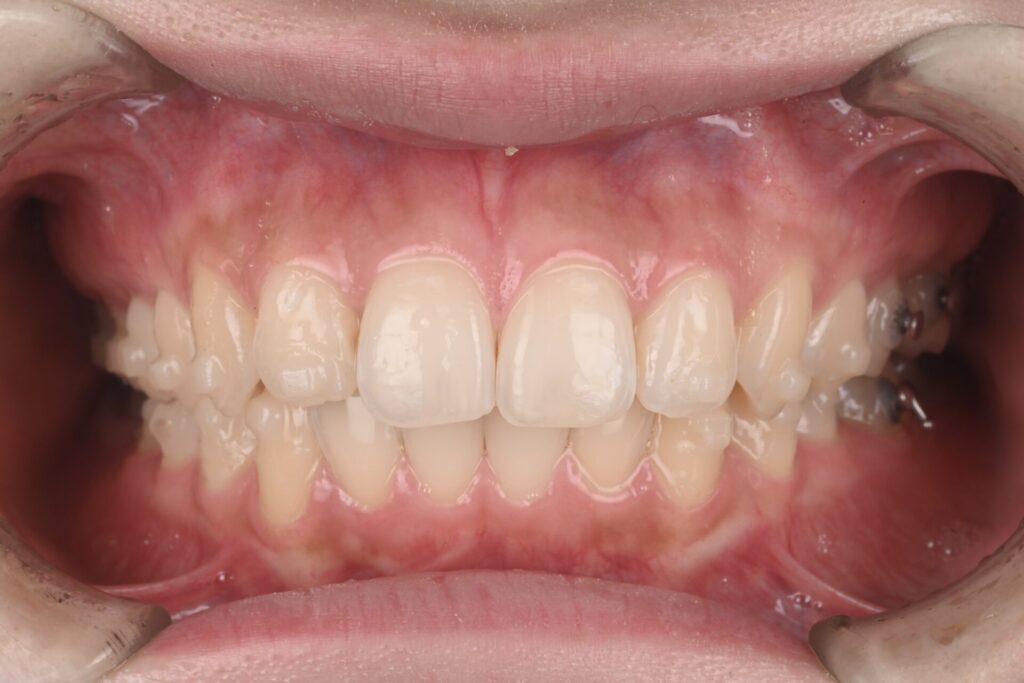

骨格分析に基づき、欠損部にインプラントを入れず、インビザライン(マウスピース矯正)でスペースを閉鎖しながら歯並びと咬合を同時に改善しました。

他院で「インプラントは難しい」と説明を受けた20代女性から、インプラント希望でご相談。精査の結果、矯正でのスペース閉鎖が適応と判断しました。

- 結果:スペース閉鎖+配列改善により、見た目・発音・咬合安定・清掃性が向上